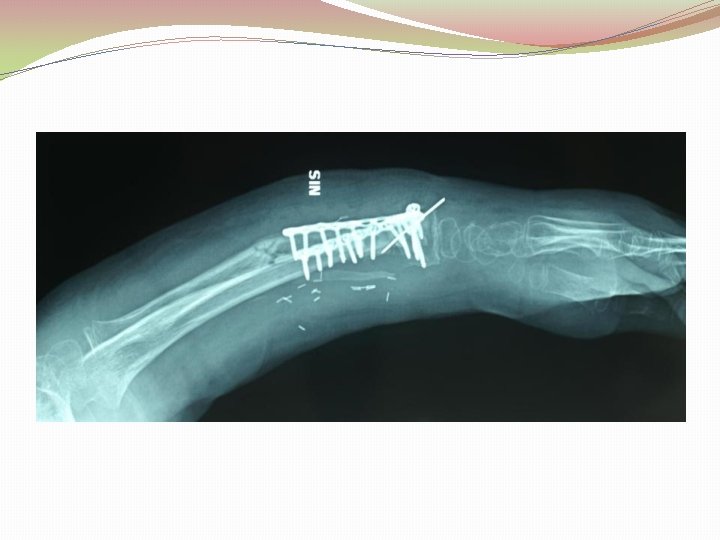

Ķirurģiska ārstēšana Osteomielīta pacientiem jāveic radikāls debridement ķirurģiski, kas ietver visu procesā iesaistīto audu rezekciju: �Mīksto audu rētas rezekcija �Cīpslu kalcinātu rezekcija �Distantu sekvestru rezekcija �Kaula rezekcija līdz vizuāli veseliem audiem – readzama punktveida asiņošana ´Paprika sign’. Bogdan Maciuceanu, Lucian Jiga, Alexandru Nistor, Jenel Marian Pastrascu, Mihail Ionac Chronic Osteomyelitis of Long Bones Timisoaral Medical Jornal, 2005

Ķirurģiska ārstēšana Veiksmīgas ķirurģiskas ārstēšanas stūrakmens ir mirušas telpas ‘Dead space’ aizpildīšana, kas izveidojas pēc debridemet veikšanas Brad Parsons, Elton Strauss, Surgical management of chronic osteomyelitis, The American Journal of Surgery 188 (Suppl to July 2004) 57 S– 66 S

Debridement Os konstrukciju evakuācija Biopsija un mikrobioloģija Dobuma slēgšana Antibakteriāla terapija Stabilizācija (Ārējā fiksācijas aparāts) Maina vai apstiprina antibakteriālo terapiju Mīksto audu rekonstrukcija 6 nedēļas antibakteriāla terapija (pēc debridement) Pseidartroze Konsolidācija Atkārtot ārstēšanu Luca Lazzarini, Jan T. Mader, Joson H. Calhaun Osteomielitis in Long Bone, The journal of bone&joint surgery, Volume 86 A, nr 10, 2004